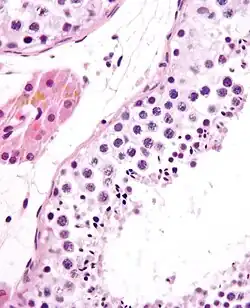

![]() A mature human Spermatozoon | |

Spermiogenesis

During spermiogenesis, the spermatids begin to form a tail by growing microtubules on one of the centrioles, which turns into basal body. These microtubules form an axoneme. Later the centriole is modified in the process of centrosome reduction.[16] The anterior part of the tail (called midpiece) thickens because mitochondria are arranged around the axoneme to ensure energy supply. Spermatid DNA also undergoes packaging, becoming highly condensed. The DNA is packaged firstly with specific nuclear basic proteins, which are subsequently replaced with protamines during spermatid elongation. The resultant tightly packed chromatin is transcriptionally inactive. The Golgi apparatus surrounds the now condensed nucleus, becoming the acrosome.

Maturation then takes place under the influence of testosterone, which removes the remaining unnecessary cytoplasm and organelles. The excess cytoplasm, known as residual bodies, is phagocytosed by surrounding Sertoli cells in the testes. The resulting spermatozoa are now mature but lack motility. The mature spermatozoa are released from the protective Sertoli cells into the lumen of the seminiferous tubule in a process called spermiation.

The non-motile spermatozoa are transported to the epididymis in testicular fluid secreted by the Sertoli cells with the aid of peristaltic contraction. While in the epididymis the spermatozoa gain motility and become capable of fertilization. However, transport of the mature spermatozoa through the remainder of the male reproductive system is achieved via muscle contraction rather than the spermatozoon's recently acquired motility.